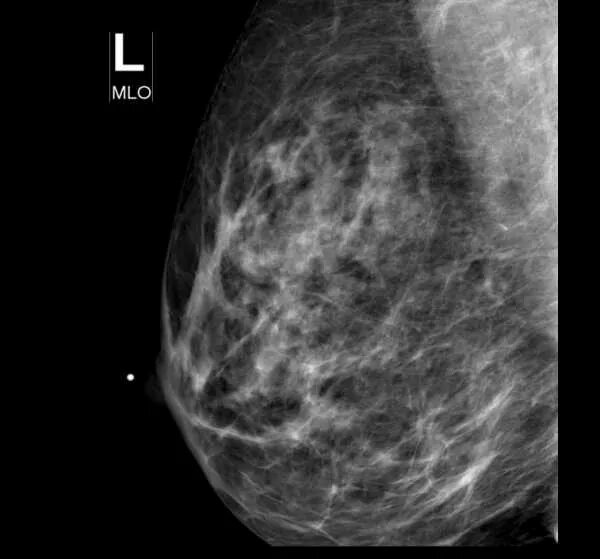

Типы плотности молочных желез маммография. высокая плотность rg молочных желез. липома молочной железы на маммографии фото. гамартома молочной железы, фото снаружи.